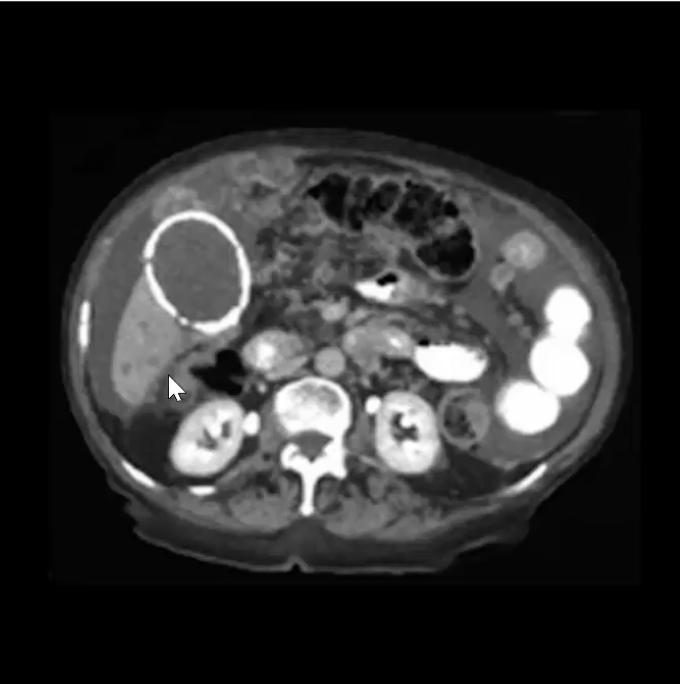

Choledocholithiasis

the presence of gallstones in the common bile duct, which can lead to obstruction and cause jaundice or pancreatitis.

Choledochal Cyst

a congenital dilatation of the bile duct that can lead to complications such as cholangitis and pancreatitis - even when removed predisposes to cancer

Extrahepatic Cholangiocarcinoma

Klatskin Tumor

A type of extrahepatic cholangiocarcinoma that occurs at the junction of the left and right hepatic ducts. It often leads to biliary obstruction and jaundice.